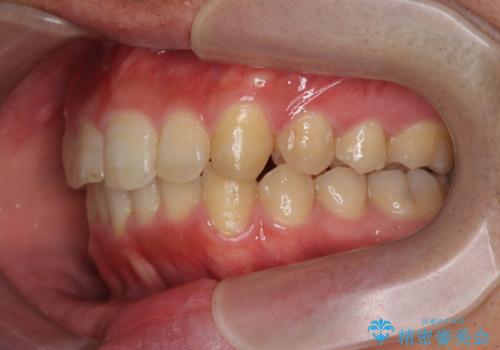

ガタつきの大きい前歯 インビザラインによるマウスピース矯正治療

- ガタつきの目立つ前歯の改善を求めて来院されました。

上顎前突、がたつきを改善すべく上顎臼歯の後方移動・ディスキングを行い歯並びの改善を計画します。

食事・歯ブラシ時以外の時間にしっかりとマウスピースを装着していただけたのでガタつきは大きく改善し良好な歯並びを得ることができました。